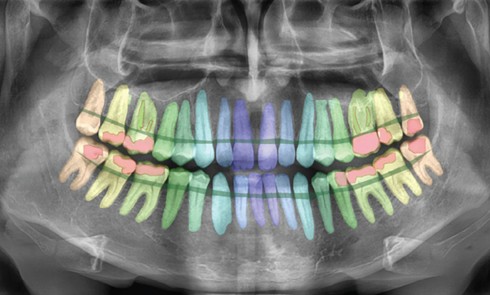

Article réservé à nos abonnés La naissance de l’intelligence artificielle en dentisterie

Partie 1 : L’empreinte optique apporte l’intelligence artificielle générative [1] à la dentisterie

En 1984, nous écrivions dans un article de Dentist News [2] : « La théorie de l’empreinte optique (CFAO) est une nouvelle...